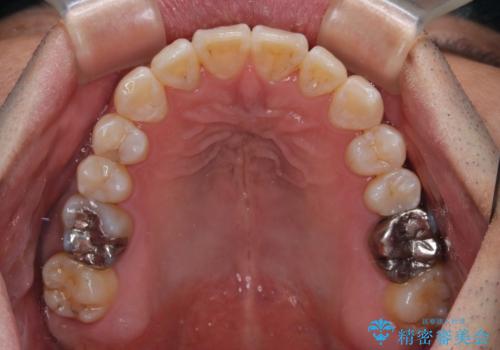

- 前歯のデコボコとクロスバイトを気にして来院された患者様です。

40代半ばであり、あまり周りに気を遣われずに治療を進めたいとのことで、インビザラインにて矯正治療を行うこととしました。

毎日22時間の装着時間をきっちりと守ってくださり、1年半かけずに思い通りの歯列に仕上げることができました。